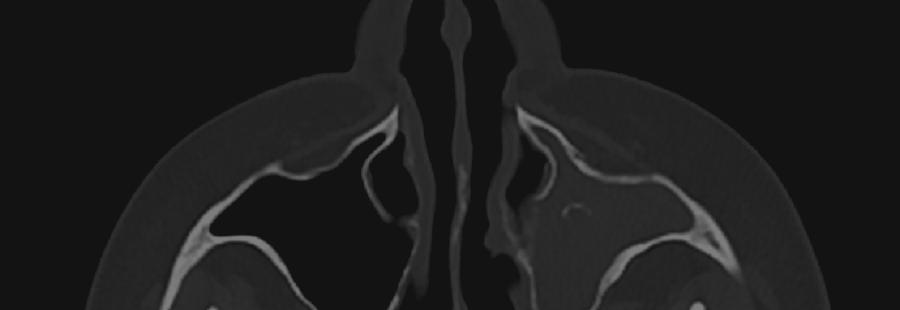

Ринопластика – це операція, проведення якої зумовлено

необхідністю змінити пропорції та контури носу, усунути деформації. Операція

носить в собі як косметичнийхарактер,такіможебути

спрямована на відновлення

носового дихання та корегування носової перегородки.